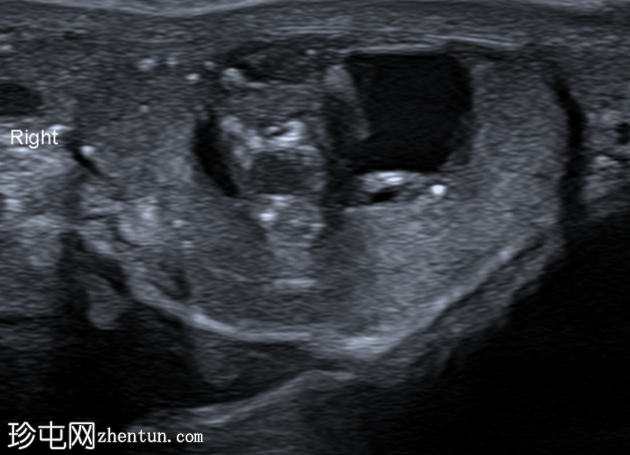

超声检查

右侧睾丸内可见一异质性肿块,大小约10 x 14 x 15 mm,包含实性和囊性成分。肿块内可见多发小钙化灶。彩色多普勒超声检查显示肿块内血流信号较少。